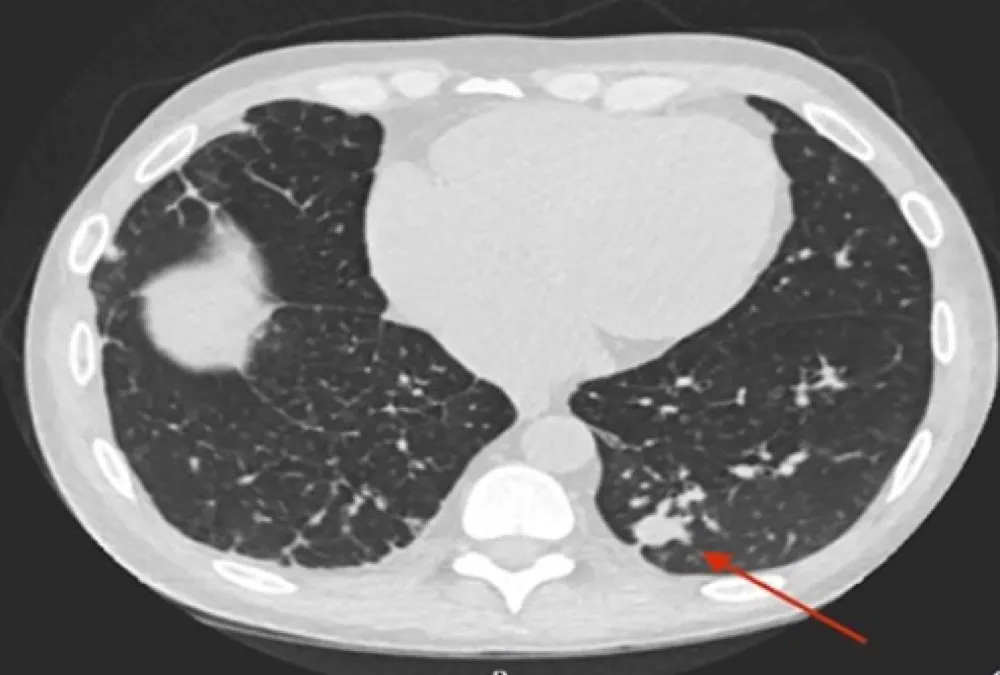

Febre, nódulo pulmonar e granuloma em um paciente transplantado renal

Febre, nódulo pulmonar e granuloma em um paciente transplantado renalFebre, nódulo pulmonar e granuloma renal em um transplantado renal

Valkercyo Feitosa

3 anos atrás